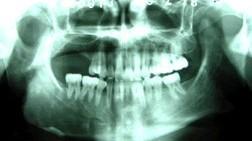

骨骼表淺部位的病變可出現畸形或腫塊,如顏面不對稱,上顎突起類似獅面,有時引起眼球突出。脊椎和肋骨受累時,胸部不對稱,局限性突起。四肢長骨受侵時,呈膨脹彎曲畸形,掌跖骨受侵者肢端隆起。深部病變早期很難發現。皮膚色素沉著也較多見,散在腰、臀、大腿等處,偏患側,且以中線為界,呈點狀或片狀深黃色或黃棕色皮斑,有時表淺,不隆起,邊緣呈齒狀,不規則,大小不等,組織結構與正常皮膚相似。性早熟僅發生在少數骨骼受損較嚴重者,絕大多數為女性,表現為陰道出血,但不是月經,嚴重者在3~4個月即出現,第二性徵出現早,外陰變大,乳房發育早,腋毛和陰毛出現過早,偶有智力減低和其他內分泌症狀。軀體半側多個骨骼廣泛病變,皮膚色素沉著伴性早熟者,稱為McCnne-Albright綜合徵。

多髮型纖維異樣增殖症病變常侵犯數骨,並有侵犯鄰近數骨的現象,如侵犯同側的髂骨、股骨、脛骨及腓骨,髂骨的病變系溶骨性,呈較大的多囊狀,其中可見骨紋理,有不同程度的骨質膨脹。四肢長骨的病變常累及骨的全部,髓腔寬窄不均,其增寬處骨皮質變薄並擴張,髓腔內紋理消失,呈磨砂玻璃狀,有的部位骨質高度膨脹,其中有囊狀表現,常發生病理性骨折。顱骨病變中,顱底骨質緻密,枕、顳骨變形,呈緻密與疏鬆相混的陰影。